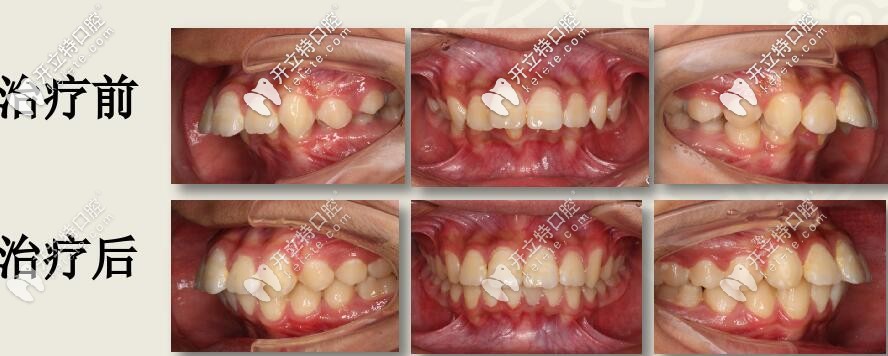

肉眼可見(jiàn)上前牙唇傾,輕度擁擠 下頜牙弓寬度窄,前牙區(qū)擁擠,后牙去舌傾明顯,前牙深覆蓋,深覆合

結(jié)束后,牙列整齊,深復(fù)蓋明顯改善。